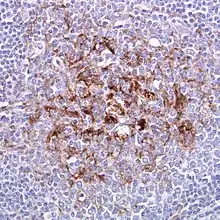

| Biopsy of the tonsil in variant CJD. PrPsc deposits are stained brown and are visible. | |